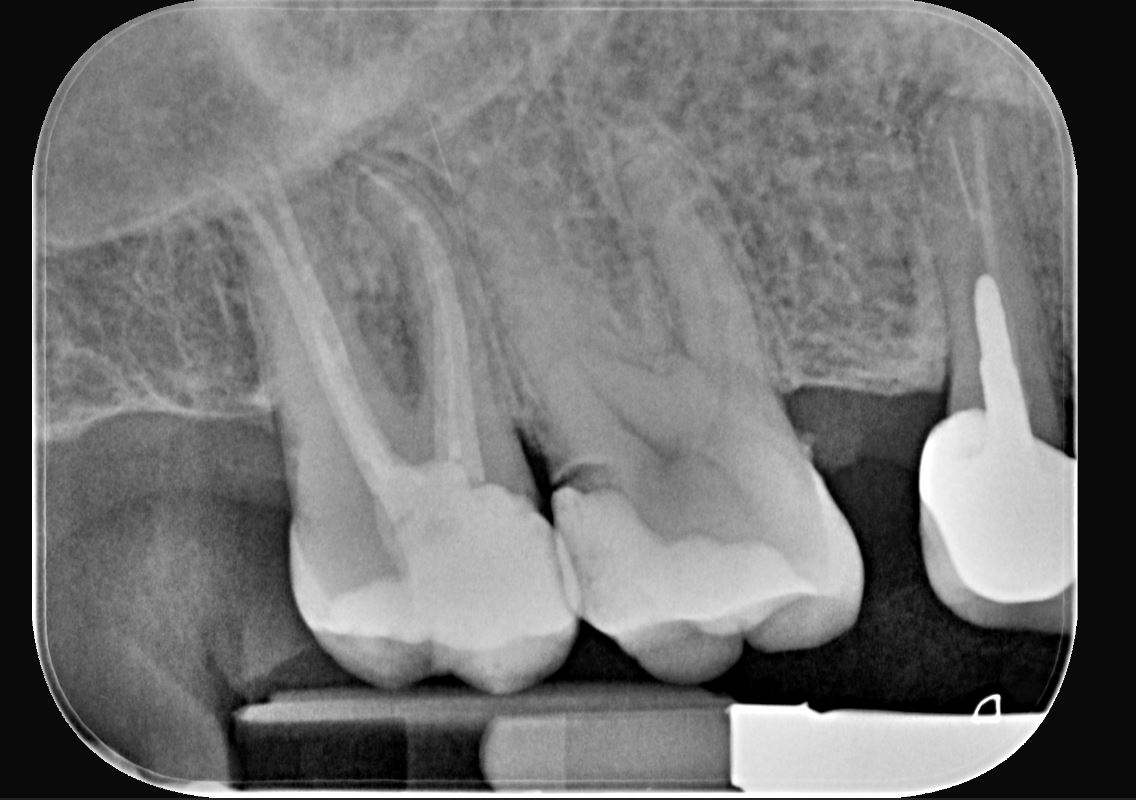

Una paziente di 44 anni si presenta alla nostra attenzione per la sostituzione di un vecchio restauro danneggiato. All’esame clinico si osserva la frattura della cuspide disto-palatina dell’elemento 1.6, associata a infiltrazione marginale di un restauro in composito incongruo. Le radiografie periapicali non evidenziano radiotrasparenze periapicali, ma mostrano possibili aree di demineralizzazione in zona marginale e all’interfaccia dente-restauro (1, 2, 3) (Figure 1-2).